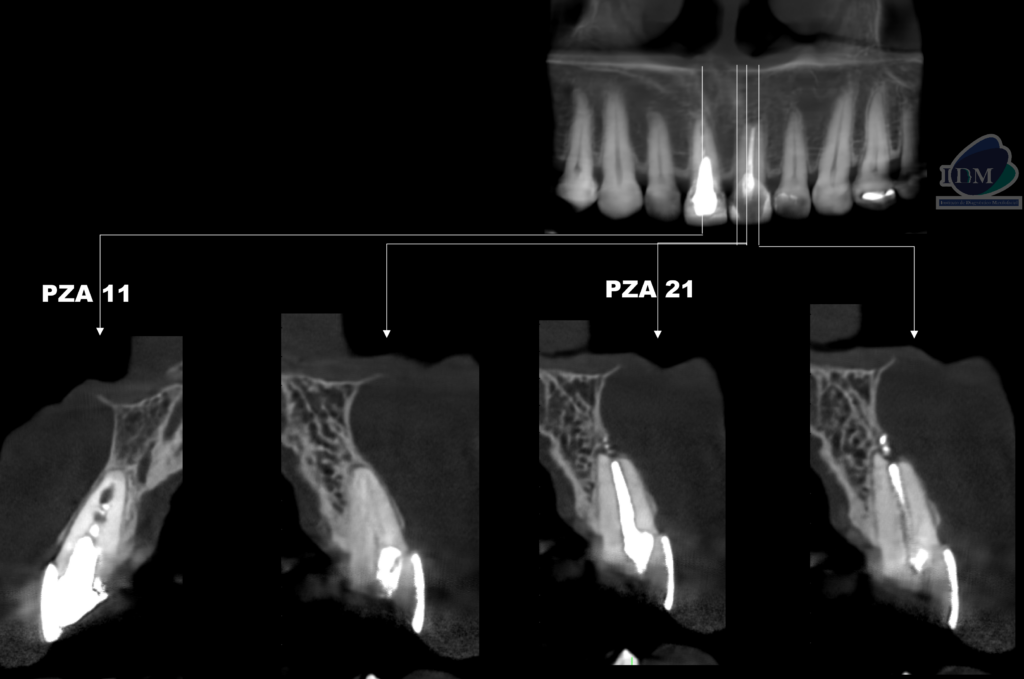

A la evaluación de la tomografía volumétrica (cone beam) en los cortes axiales (Figura 2) y transaxiales (Figura 3) se observa la pieza 11 con obturación parcial de conducto radicular y ensanchamiento del espacio para el ligamento periodontal y pieza 21 con obturación de conducto y reabsorción radicular externa en tercio apical, pérdida de continuidad de la cortical de tabla ósea vestibular. Además, se observa imágenes hiperdensas a nivel de periápice con orientación hacia tabla ósea vestibular de pieza 21 compatible con cuerpo extraño (material de obturación).

CORTES TRANSAXIALES